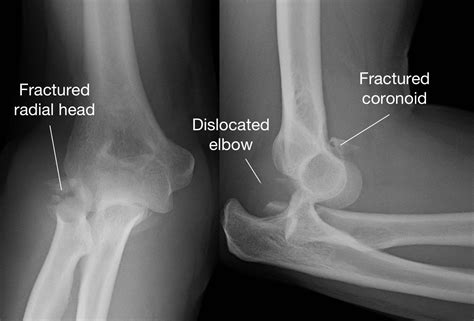

• Imaging Tests: X-rays or other imaging tests may be ordered to assess the extent of the injury and check for any associated fractures.

• Imaging Tests: Ordering X-rays or other imaging tests to check for any underlying issues.